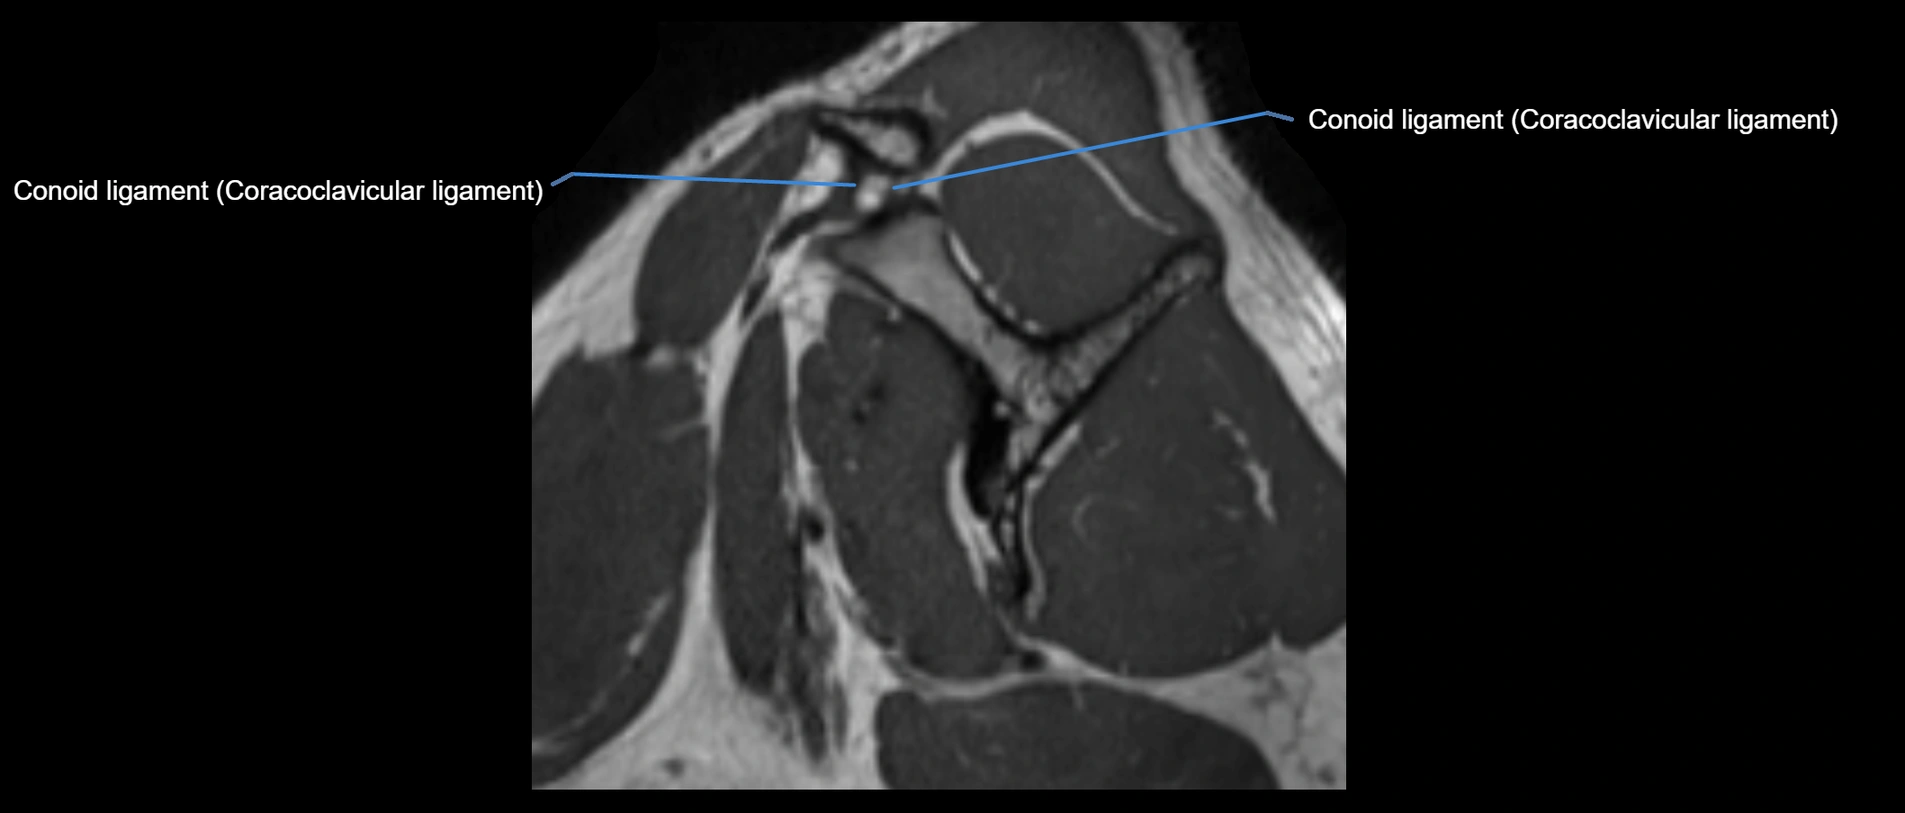

MRI images

image